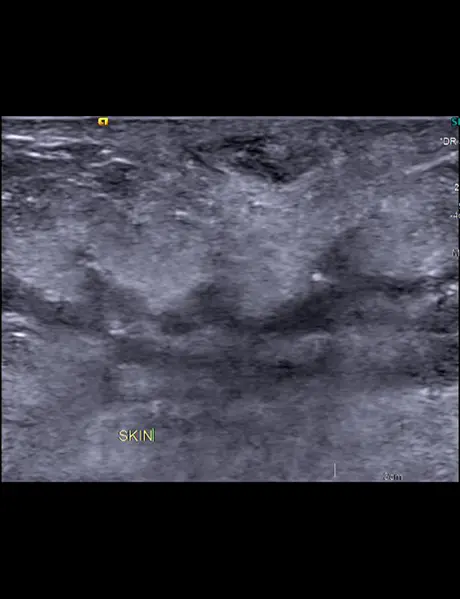

Left breast USG showing mass forming area consisting of multiple thickened dilated ducts extending into the subcutaneous region (straight white arrow). There is parenchymal edema surrounding this area of abnormality.

A) & B) Large area of abnormality in upper half of left breast with dominant central mass (straight white arrow). Multiple dilated and thickened ducts (straight red arrow)are seen extending from the mass.

C) Multiple lymph nodes (curved white arrow) with thickened cortices in left axilla